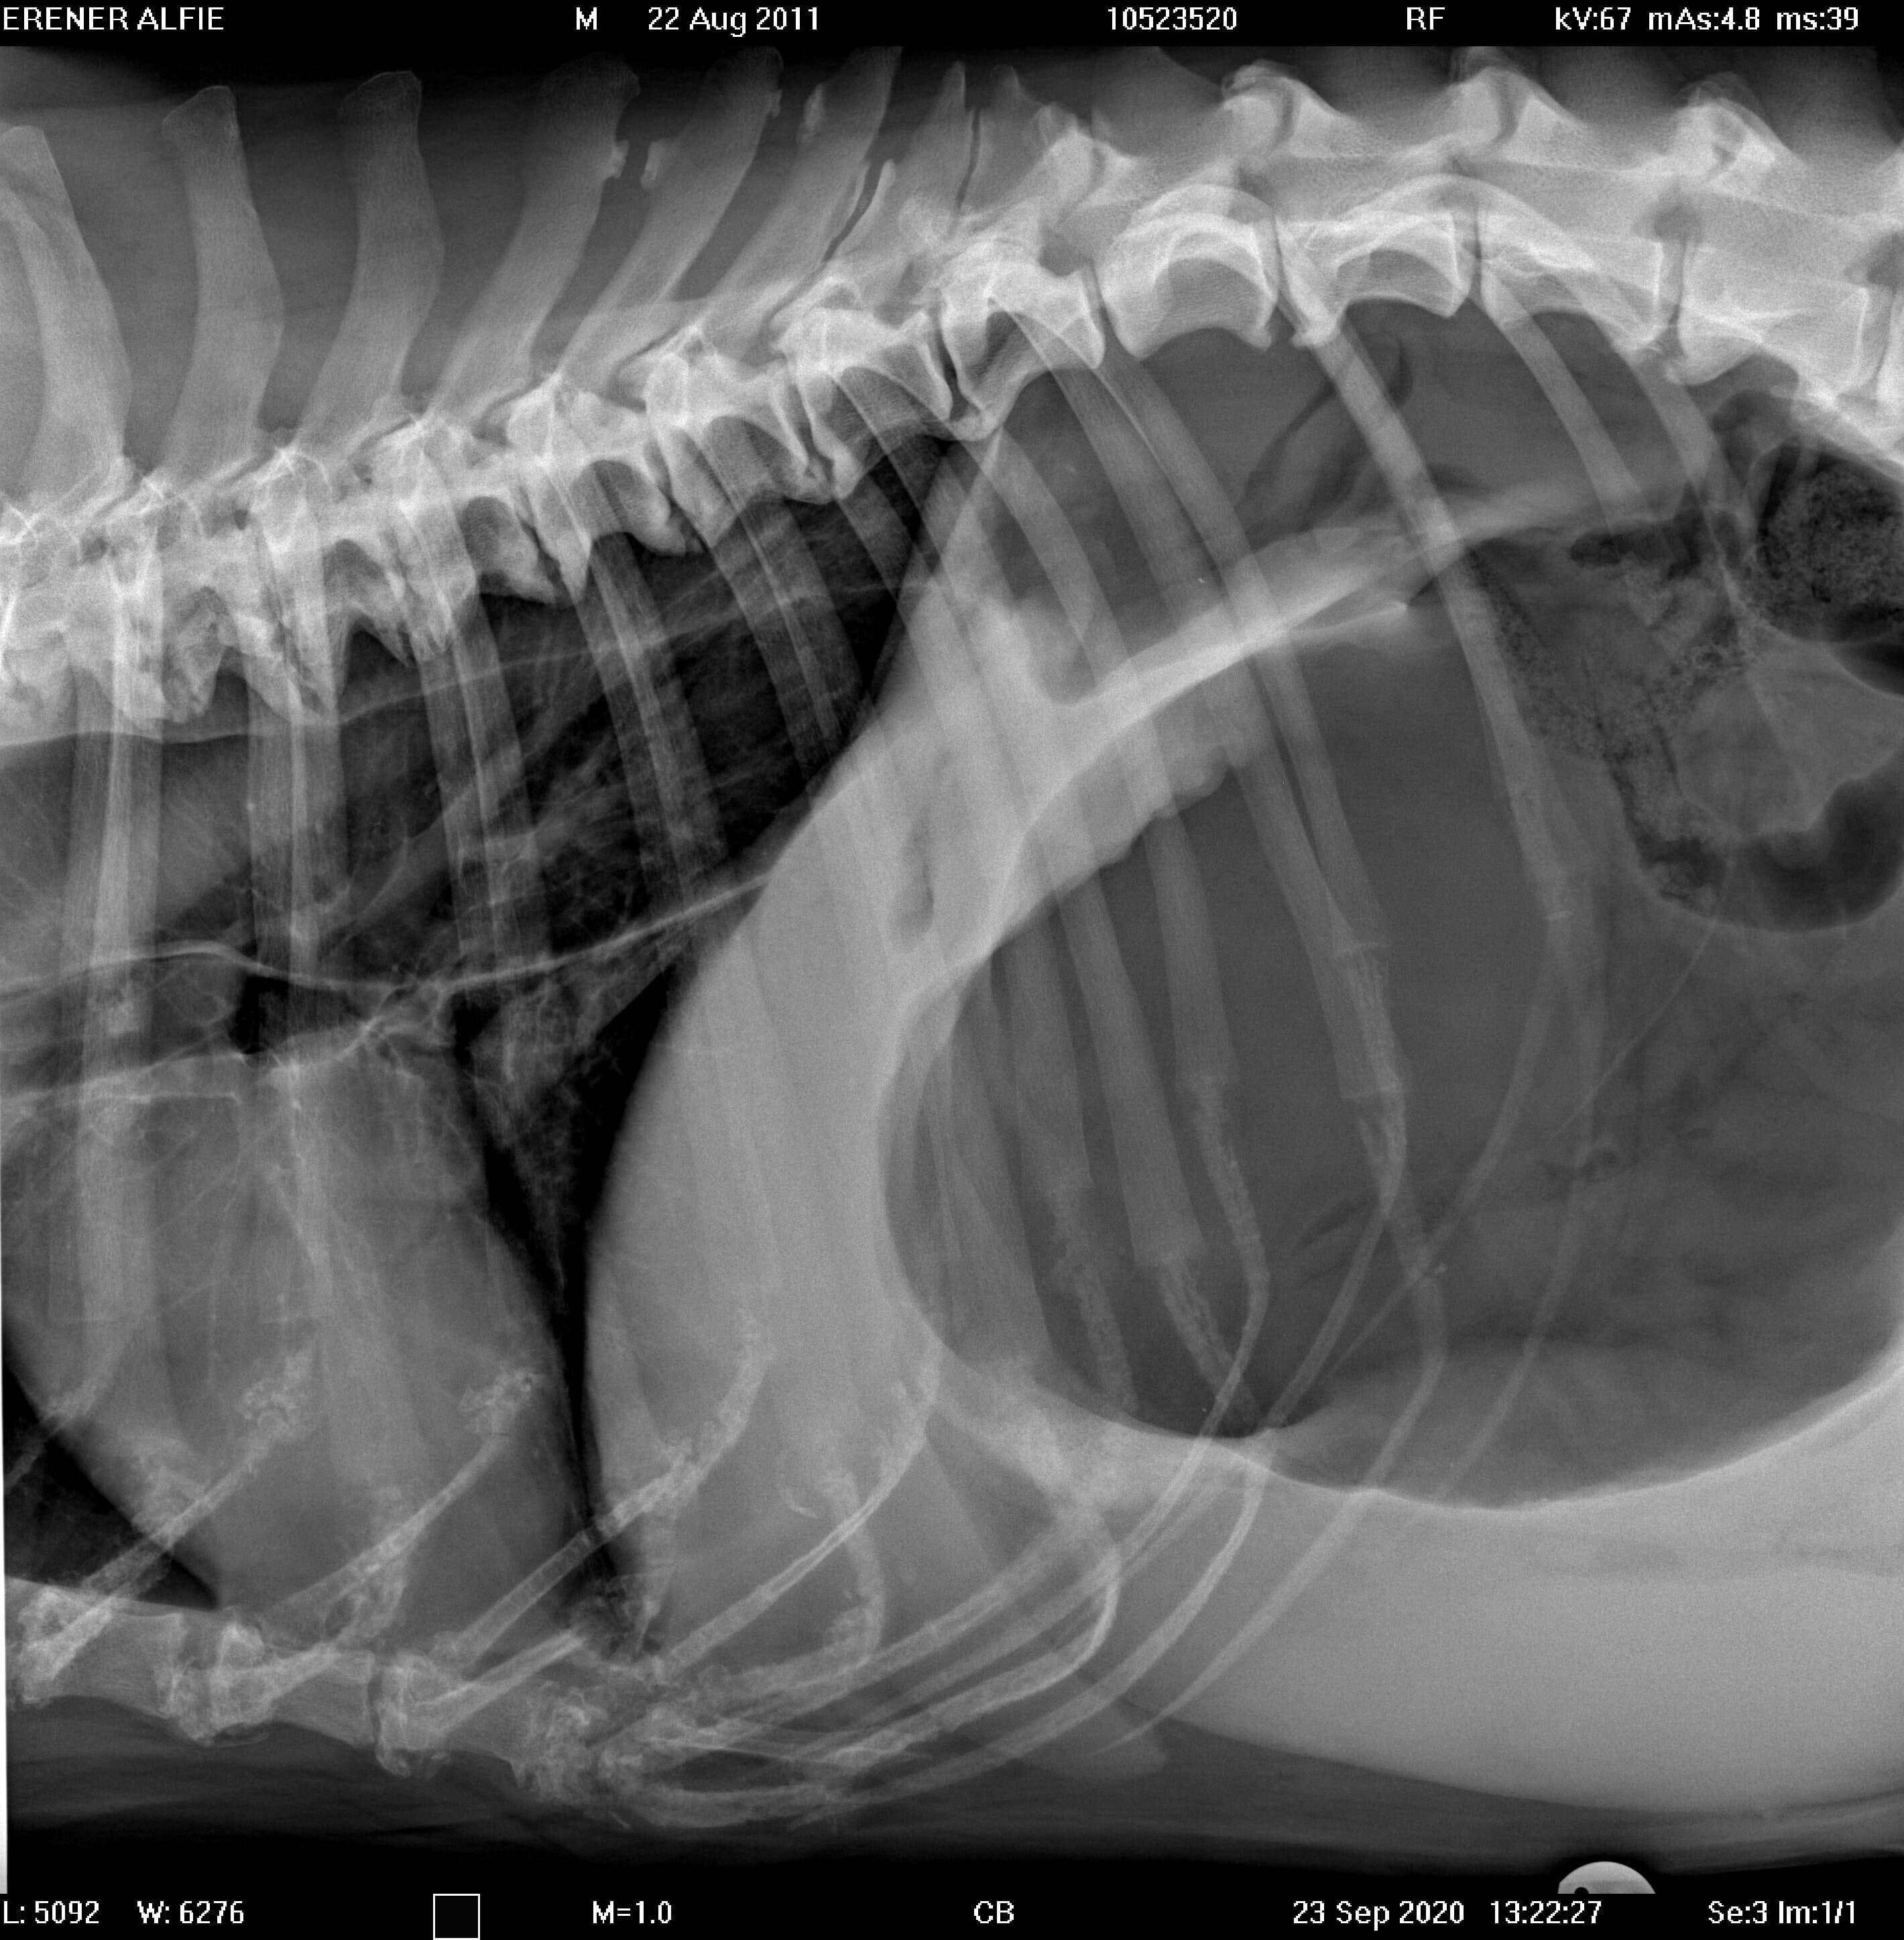

Proximal duodenal and gastric outflow obstruction can cause persistent vomiting with low serum Na, Cl and K; these electrolyte changes should be considered very suspicious even in the absence of imaging findings for obstruction. Abdominal radiographs should include orthogonal views (a right lateral and a ventro-dorsal or dorso-ventral image). Classic radiographic signs for surgical disease can include the “double bubble” for GDV ( Figure 1), two distinct populations of small intestine with obstruction (small and large diameter gut evident with, for example, intussusception, intestinal mass or foreign body; Figure 2) or free abdominal gas with a lack of serosal detail with septic peritonitis. Free abdominal gas can be very obvious ( Figure 3) but a more subtle pneumoperitoneum is best recognised using a horizontal beam radiograph with the patient in lateral recumbency ( Figure 4). Of course, a lack of radiographic changes does not fully exclude a gastrointestinal emergency and abdominal ultrasound can help to identify the problem or guide further diagnostics (eg abdominocentesis of free abdominal fluid). Septic peritonitis due to intestinal leakage will result in an effusion with cytological identification of neutrophils and/or bacteria. If intracellular bacteria can’t be definitively identified but there remains a concern for septic peritonitis, glucose and lactate assessment can be helpful.